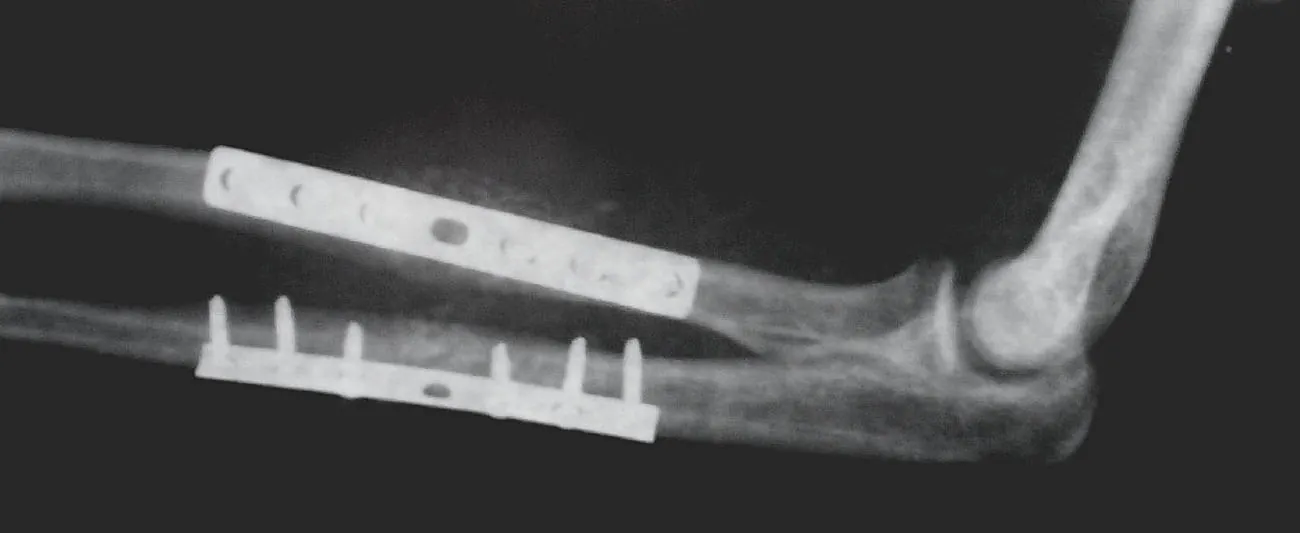

Internal Fixation

A surgery of internal fixation involves the placement of metal pieces into the bone to help it heal as it grows back together (Figure 13.12). The types of metal pieces vary depending on the fracture’s location and size, but they can be rods, plates, screws, or pins. In some cases, the metal pieces are removed after healing occurs; in other cases, the metal pieces are left in place forever.

X-ray showing internal fixation of the radius and ulna

Figure 13.12 This x-ray shows an internal fixation of the radius and ulna. (credit: “X-ray3” by Mikael Haggström/Wikimedia Commons, Public Domain)